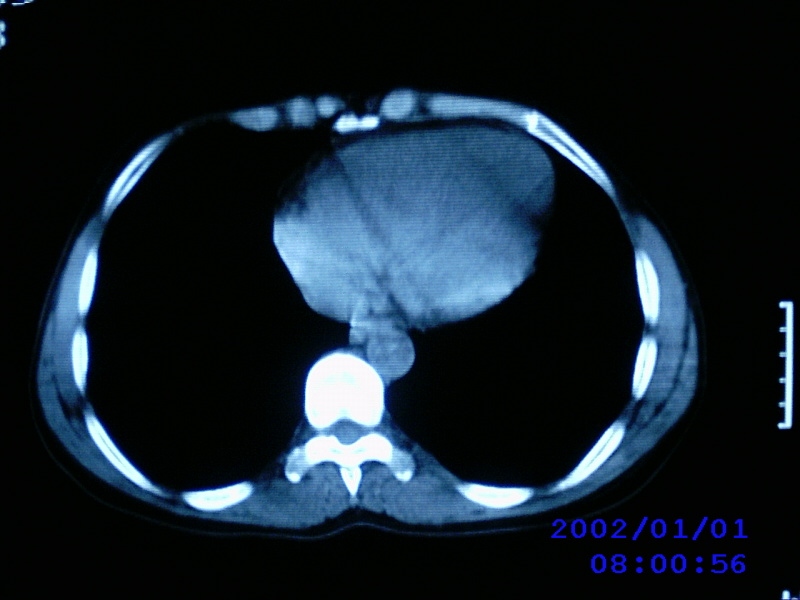

患者,女性,44岁,上腹部疼痛1个多月。b超提示胰头区域有低密度占位性病变。

病人是农村的不愿意做增强,只好麻烦老师们看一下!!

不增强的话价值不大,而且图像没有去色,考虑淋巴瘤可能,胰头病变伴淋巴转移不排除

图片怎么照成蓝色的?看了不太清

把十二指肠挤够呛,支持胰头占位可能----进一步检查。

考虑胰头癌伴肝门淋巴转移

胰头占位,胰管不扩张吗?

考虑胰头癌伴肝门腹主动脉旁淋巴转移

老师病人没有黄疸,没有发烧,只是有点畏寒,中上腹部痛,b超提示胰腺没有问题,只是第二肝门近胰头部见一大小约3.7cmx2.5cm椭圆形低回声,形态欠规则,边界可见.

胰头及其上部见一类圆性软组织占位,密度欠均匀,胆道系统无扩张,胰头钩突部大小正常,胰管无扩张,十二指肠受压---考虑1 肠道间质瘤,不除外胰头无功能腺瘤。